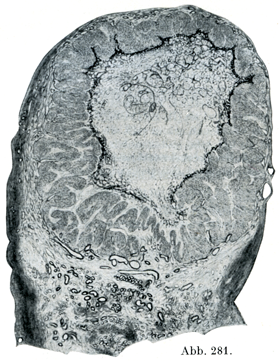

卵じしんはまず卵管にはいり,ついで子宮に達する.ところが一方,破裂した卵胞の上皮からは,その個々の細胞の容積が増大することだけによって(細胞の数はふえない)黄体Corpus luteum, Gelbkörper(図281)ができる.これには卵胞の結合組織の壁も関与している.黄体の直径はほぼ1cmに達することがある.その中心は初めは血液で充たされた腔所である.あとになって現われるヘマトイディンの結晶は初めに流出した血液が変化して生じたものである.

黄体は初めは赤体Corpus rubrumというが,2日目遅くとも3日目には黄体になる.それとともに大きくなった卵胞細胞の内部には多数の脂肪粒子が現われて,血液は吸収され,ついでルテイソ細胞による黄色調がはつぎりと現われてくる.これがいわゆる“開花の状態Zustand der Blüte”である.その期間がどのくらい続くかはまだ確定していない.それに続いて血管が減少して黄体が萎縮し,脂肪化が起こって退縮する.その最後の残りものとして結合組織性の白い痕ができる.これを白体Corpus albicansという.初めの出血の残りものの量が多い場合セこは,昔の解剖学では黒体corpora nigraと呼んでいた.黄体を妊娠黄体Corpus luteum graviditatisと月経黄体Corpus luteum menstruationisに分ける.妊娠黄体はちょうどその卵胞から出た卵子が受精して,子宮のなかで発育しているときに生ずるものである.月経黄体は持続が短くて,大きさもいっそう小さい.

[図281]黄体 卵胞破裂後14日目=性周期28日目.×5